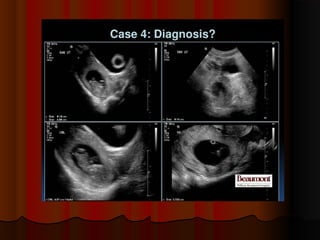

The above ultrasoundand color Doppler images show theThe above ultrasound and color Doppler images show the lower margin of the placenta partially covering the internallower margin of the placenta partially covering the internal os, suggestingos, suggesting partial placenta previapartial placenta previa..